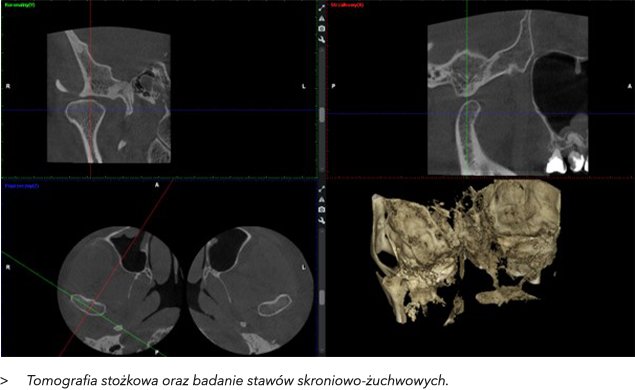

3. CBCT – Tomografia Stożkowa 3D w Ortodoncji

CBCT (Cone Beam Computed Tomography) to zaawansowana metoda obrazowania, która w ortodoncji zyskuje na popularności, oferując trójwymiarowe obrazy struktur kostnych, w tym stawów skroniowo-żuchwowych (TMJ). CBCT pozwala na dokładną ocenę stawów skroniowo-żuchwowych, które pełnią kluczową rolę w funkcjonowaniu układu żucia. Dolegliwości związane ze stawami skroniowo-żuchwowymi mogą prowadzić do bólu, trzeszczenia, ograniczenia ruchomości żuchwy, a także problemów ze zgryzem.

Korzyści z zastosowania CBCT w diagnostyce i leczeniu problemów z TMJ to:

•  Dokładna ocena strukturalna – CBCT umożliwia szczegółową wizualizację stawu skroniowo-żuchwowego w 3D, wykrywając zmiany takie jak uszkodzenia chrząstki, zwichnięcia, zmiany zwyrodnieniowe, czy zmiany w położeniu głowy kości żuchwy.

•  Ocena funkcji stawu – CBCT umożliwia monitorowanie funkcji stawu w czasie rzeczywistym, co pozwala na dokładne śledzenie jego ruchomości i wykrywanie nieprawidłowości.

•  Diagnostyka patologii – Umożliwia wykrycie wczesnych zmian patologicznych, takich jak zapalenia, co może zapobiec dalszemu rozwojowi problemów stawowych i ułatwić planowanie leczenia.

•  Planowanie leczenia – W przypadku konieczności leczenia chirurgicznego stawu skroniowo-żuchwowego, CBCT pozwala na precyzyjne zaplanowanie zabiegu. Pozwala również na monitorowanie efektów leczenia, szczególnie w ortodoncji, gdzie prawidłowe ustawienie stawów skroniowo-żuchwowych jest kluczowe dla sukcesu terapii.

•  Ocena postępu leczenia – CBCT stawów skroniowo-żuchwowych umożliwia regularne monitorowanie efektów leczenia, zarówno ortodontycznego, jak i operacyjnego, poprzez porównanie nowych obrazów z wcześniejszymi.